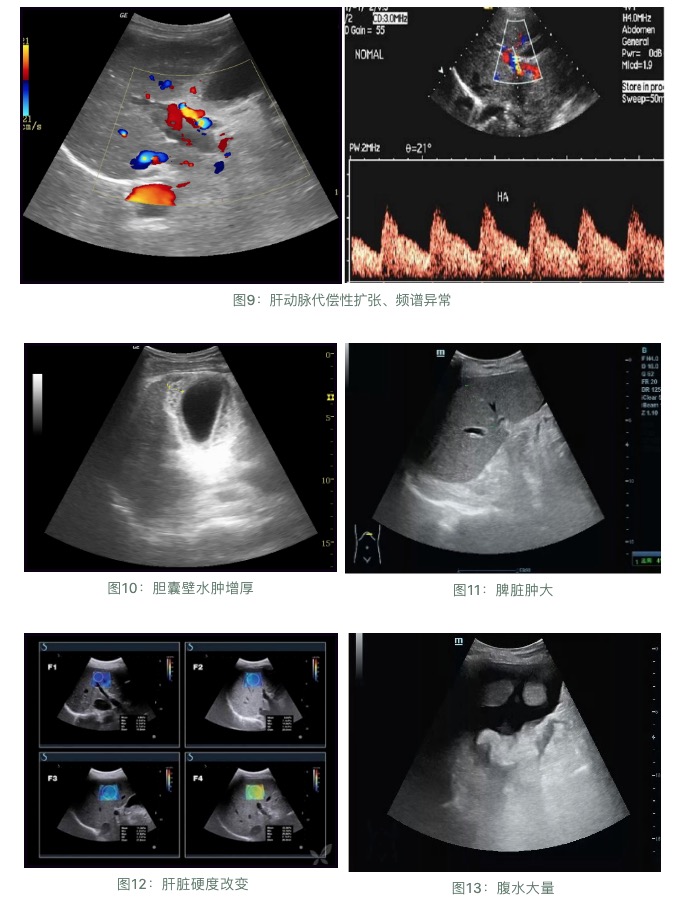

超聲檢查:

肝臟受病毒感染和發(fā)生炎癥后,就會(huì)造成肝臟內(nèi)部的結(jié)構(gòu)損傷,從局部的纖維化、結(jié)節(jié)性肝硬化到最后的全面硬化,超聲檢查是早期發(fā)現(xiàn)肝硬化的最直接指標(biāo)。

肝臟彈性檢查、肝穿刺病理學(xué)檢查等等。